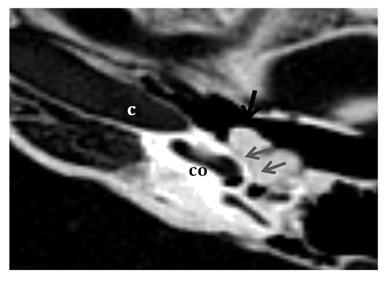

Figure 1 CT temporal bone , Axial images going from caudal to cranial (a,b,c) and coronal images ) from anterior to posterior (d,e,f ) displaying lobulated hyper dense lesion arising from the superior wall of the middle ear cavity and pedunculated along the medial wall ( black arrows)giving CT features of osteoma .